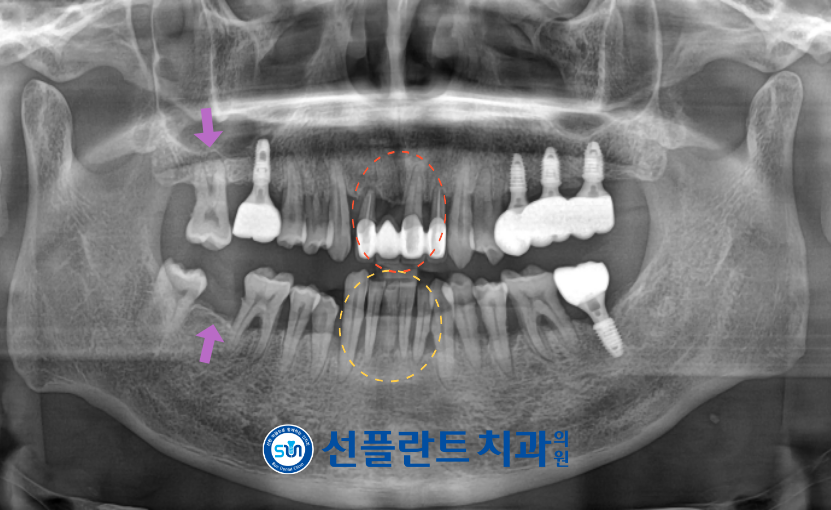

정밀한 검사를 위해

파노라마 사진을 촬영해 보았더니

치아를 단단하게 지탱하고 있어야 할

잇몸 조직들이

치석이나 세균이 쌓이게 되면서

염증이 생겨 손상되어 있는 상태였는데요.

잇몸치료를 통해 염증을 줄이고

치주조직을 건강하게 하여

치주를 안정화 시킨 뒤,

상태가 좋지 않은 치아들은 발치 후

빨간색 동그라미 표시의

위턱 앞니는 양옆의 송곳니를 이용하여

재 보철물을 진행하기로 하였으며,

노란색 동그라미 표시의

아래턱 앞니는 임플란트 식립을

도와드리기로 하였습니다.

이외에도 보라색 화살표 표시의

위아래 오른쪽 두 번째 큰 어금니(#17,47)의

임플란트 식립을 통해

어금니의 기능을

회복시켜 드리기로 하였습니다.